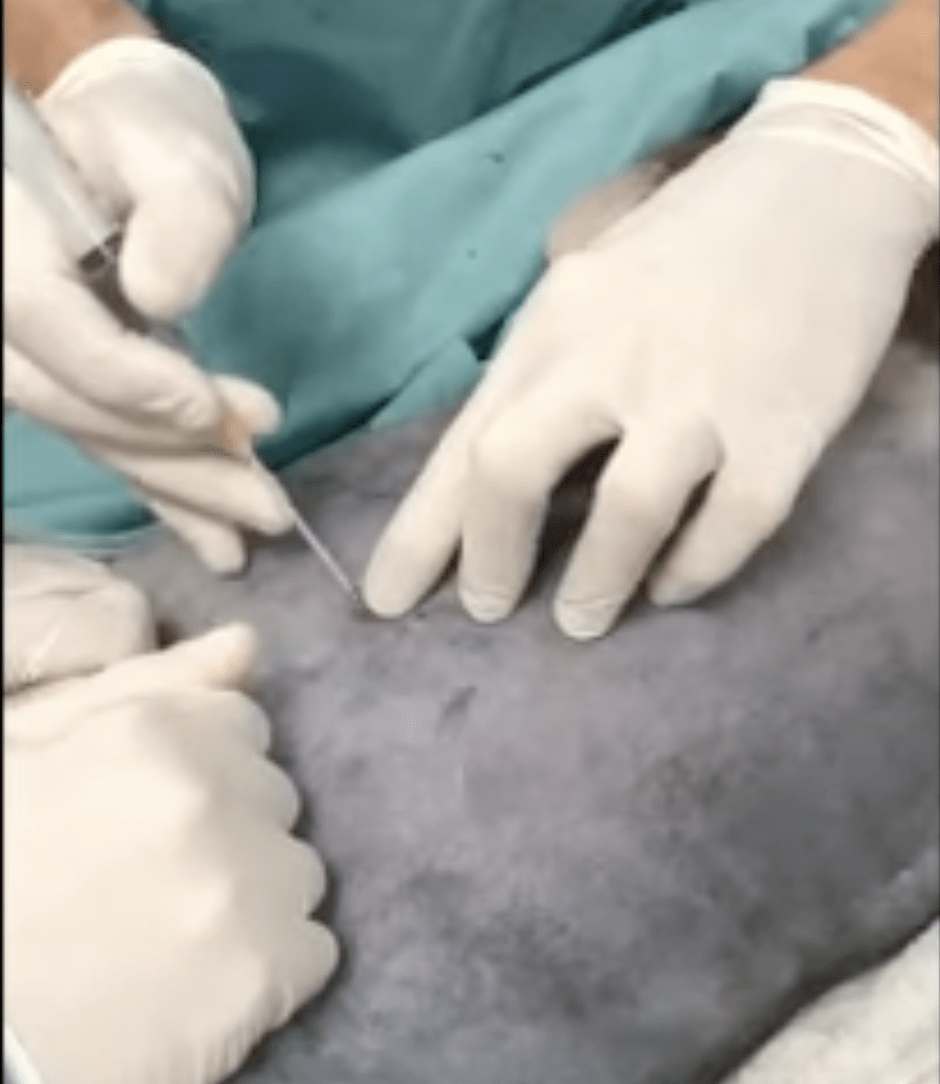

Pose d’un drain thoracique par la technique de Seldinger

Le Dr Hervé Brissot vous explique comment poser un drain thoracique en vidéo commentées. Lire la suite